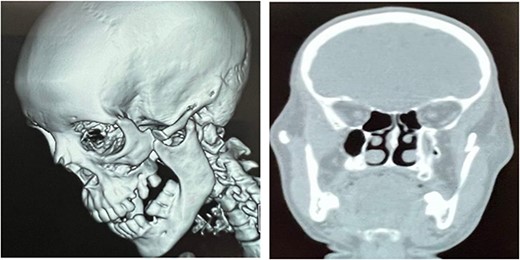

Computed tomography scan revealed a ZMC fracture associated to an anteriorly dislocated non-fractured coronoid process and condylar lateral subluxation (Fig. 3).

CT scan showing dislocation of the coronoid process above the ZMC fracture.